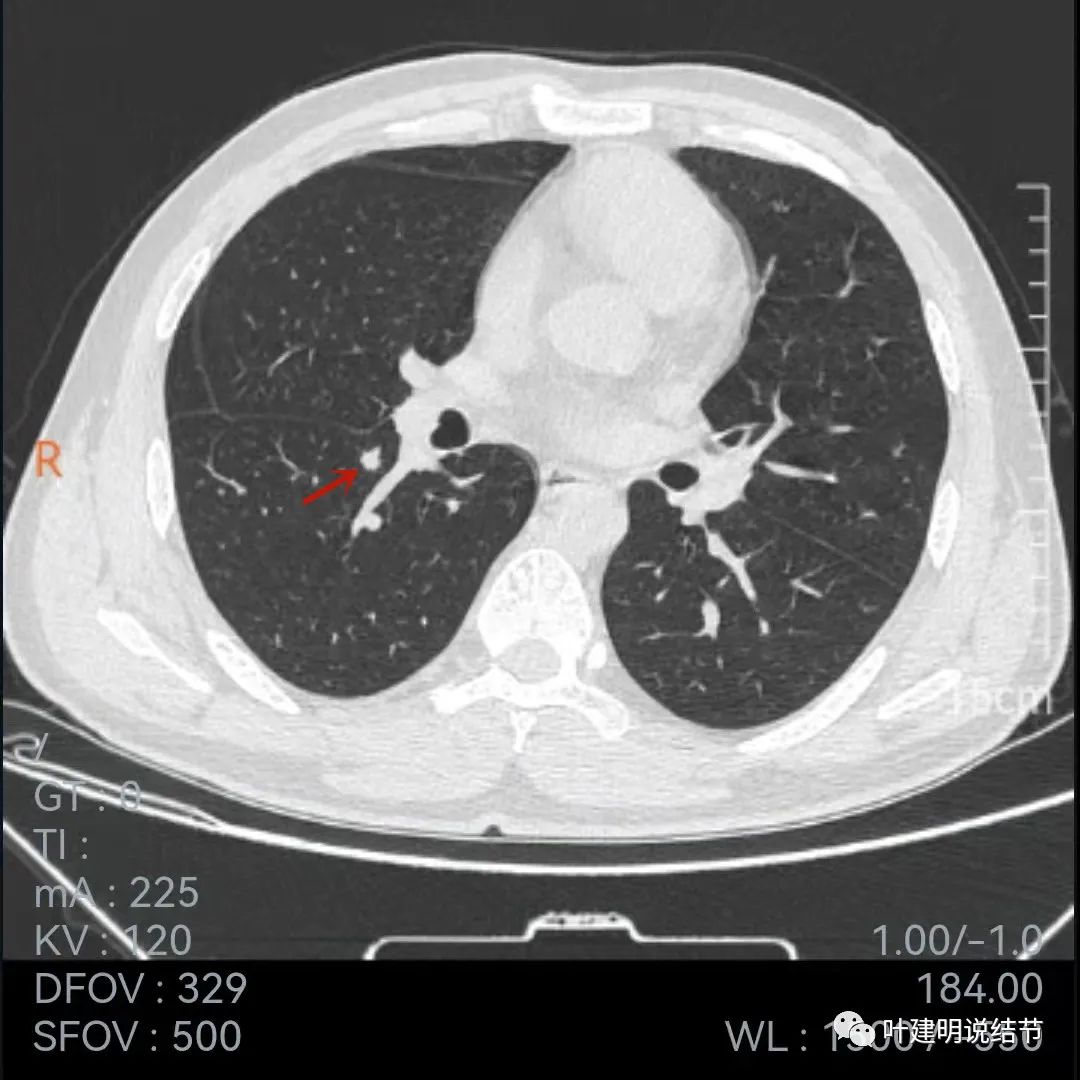

再来看薄层的,今年的薄层是1毫米一层的,去年是2毫米:

病灶胸膜凹陷更明显了,边缘不太平整(紫色箭头)

胸膜牵拉,伴病灶中间密度稍低

病灶膨胀性不够,感觉刺突相对较长,中间密度略低,边缘向内凹

上图黄色箭头示病灶中间密度要略低于周边部位,这与肉芽肿较为符合

整体还病灶似有进展,形态略有变化,但说典型的恶性样子好像又不太像。